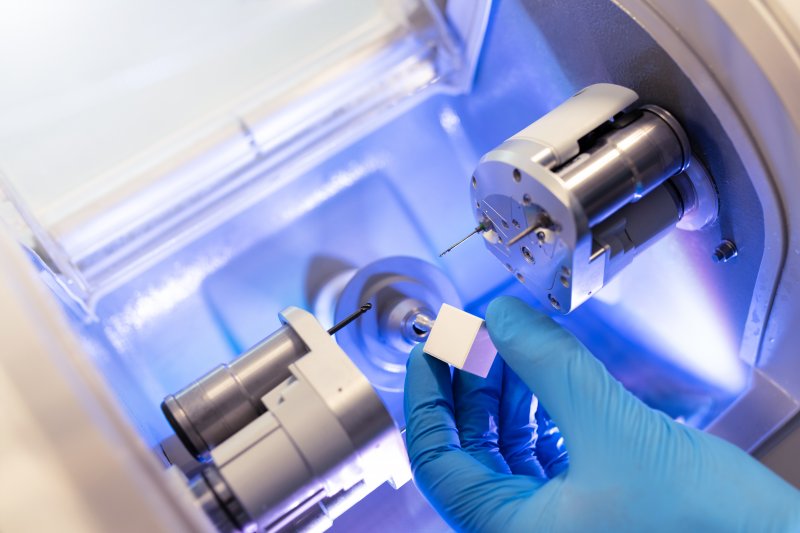

Perhaps you’re considering a CEREC dental crown instead of a normal one. That’d be a fine choice – the treatment will quickly restore your tooth to working order. Even so, you likely have concerns about this option you want to address first. Going ahead with it could seem too risky if you didn’t. Well, your Boise dentist will gladly ease your concerns for you. Just keep reading to learn four common questions about CEREC dental crowns and their answers.